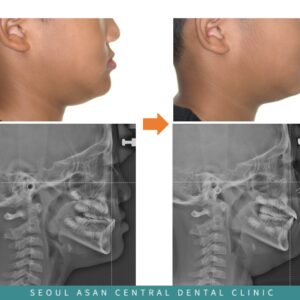

성남치과 치아 배열 문제로 인해 교합이 무너져 있다면 건강한 삶을 영위하기 위해서는 치아 건강 또한 매우 중요합니다. 하지만 치아와 잇몸을 꾸준히 건강하게 유지하는 일은 생각보다 쉽지 않은데요. 충치나 치주 질환을 비롯해 외상이나 사고, 노화 등 다양한 원인으로 치아와 잇몸이 손상되거나 상실될 경우 저작 기능이 저하되어 음식물 섭취와 소화에 어려움을 겪을 더보기…